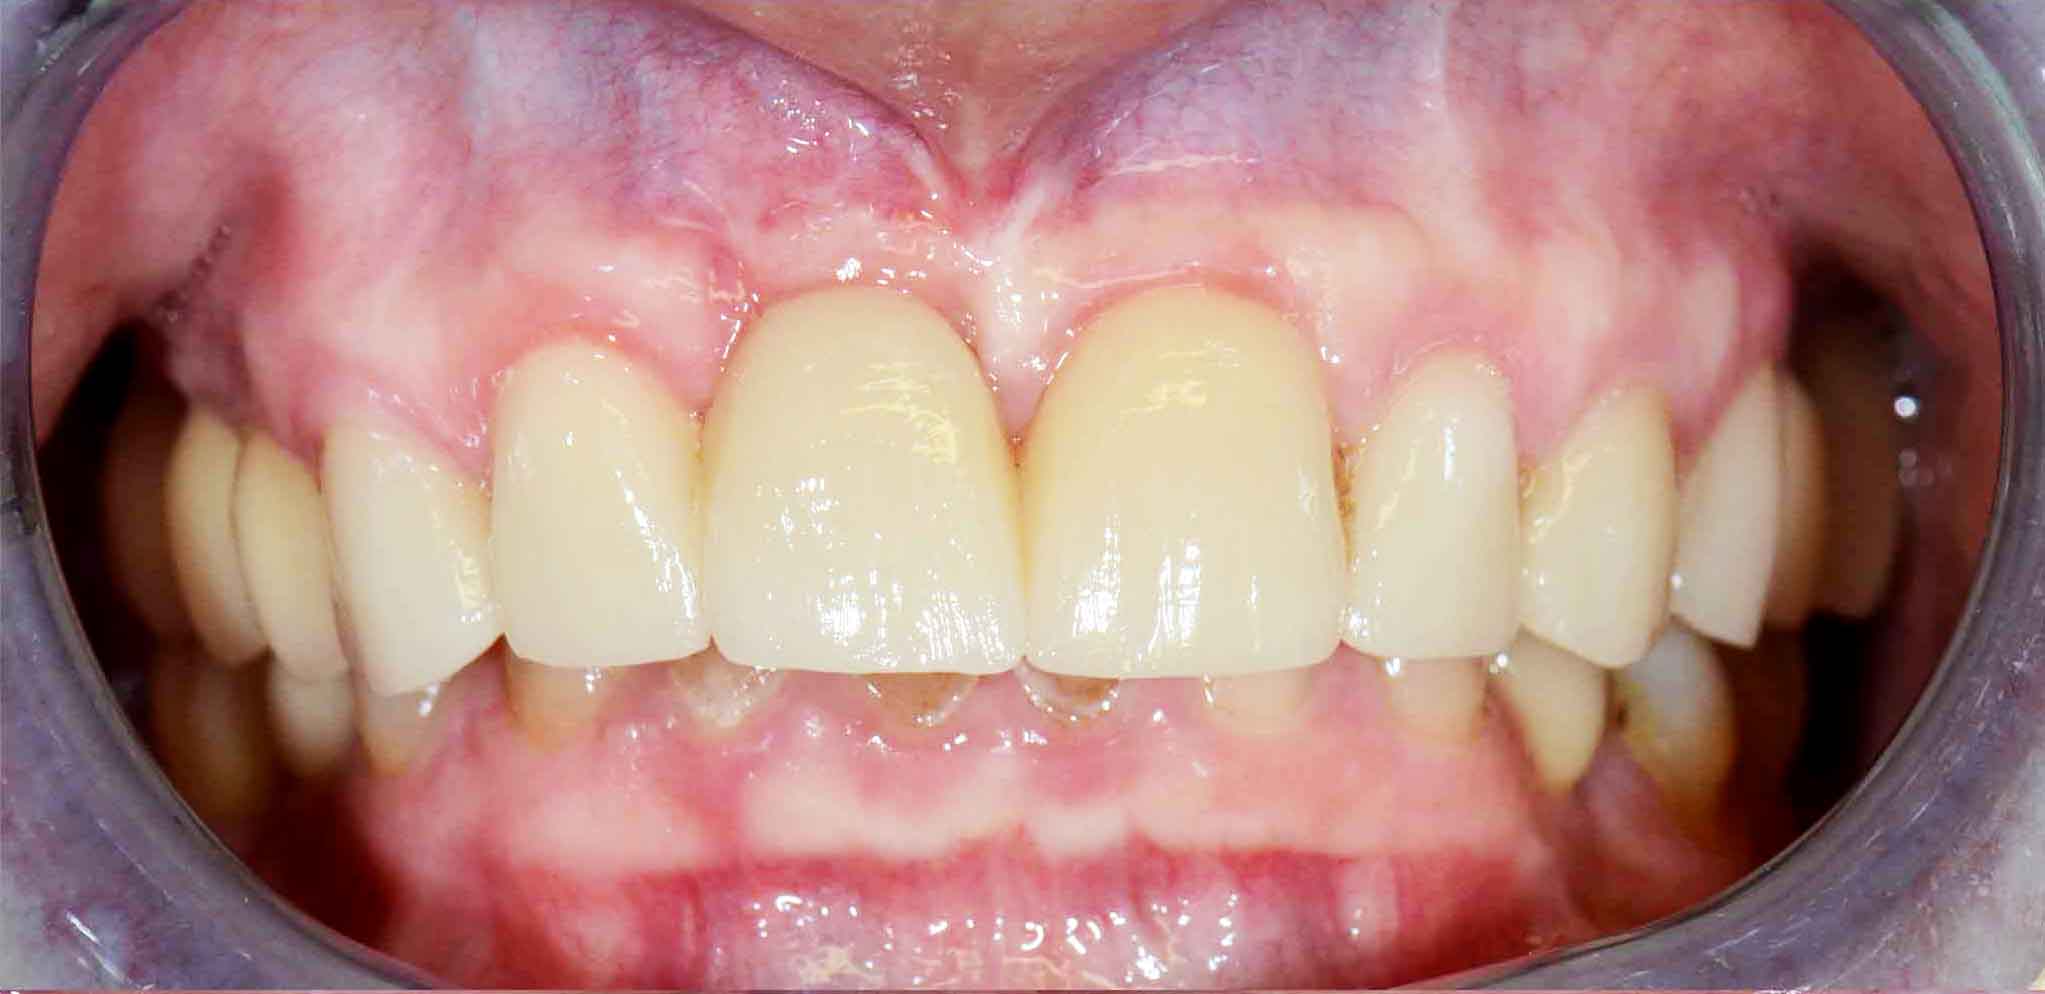

Ceramic Crowns over teeth and implants

Patient with limited functions and serious aesthetics problems.

Complex Rehabilitation – The Treatment:

The natural teeth that had a good prognosis were kept and the ones that needed their position changed were moved by a fixed orthodontic brace.

Afterward a surgery was made to place some implants. The treatment was finalized by placing the ceramic crowns over the implants and teeth.